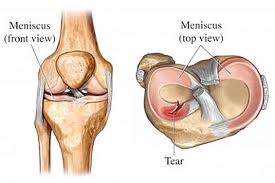

WHAT IS A PARTIAL MENISECTOMY?

A meniscal tear can occur from wear and tear in the knee, or as an acute injury. When a meniscal tear occurs the flap of tissue created can block movement in the knee and/or cause clicking which may be painful. These are called mechanical symptoms. Knee arthroscopy is very successful at relieving mechanical symptoms. Mechanical symptoms can occur in arthritic knees, however, if the knee symptoms are caused from osteoarthritis generally then the pain may persist.